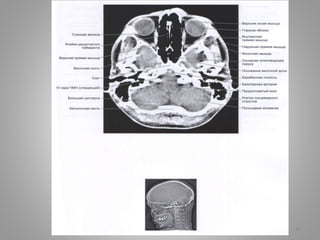

• #12 Білясередньомозкова цистерна: Чотиригорбкова цистерна (вени Галена) (c. quadrigeminalis) розташовується між мозолистим тілом і мозочком; у її ділянці можуть розташовуватись субарахноідальні кисти Обвідна (охоплююча; по Синельникову - обхідна) цистерна (c. ambient) - канал неправильної форми, що проходить по бокам ніжок мозку і даху середнього мозку; сполучається з мостовою і міжніжковою цистернами спереду і чотирегорбиковою цистерною ззаду.

• #13 Міжніжкова цистерна

• #14 Міжніжкова цистерна Охоплююча цистерна Чотирегорбикова цистерна Верхня цистерна мозочка

• #15 Велика цистерна

• #16 Передмоства цистерна Мосто-мозочкова цистерна

• #17 Міжніжкова цистерна Базилярні цистерни

• #18 Охоплююча цистерна

• #19 Охоплююча цистерна